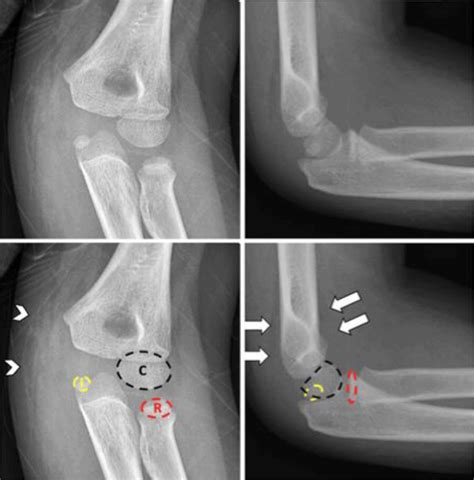

Diagnosing a Medial Epicondyle Fracture

Diagnosing a Medial Epicondyle Fracture involves a combination of physical examination and imaging tests. The diagnostic process typically includes:

• Physical Examination: The healthcare provider will assess the elbow for swelling, tenderness, and range of motion. They may also check for any deformities or instability in the joint.

• Imaging Tests: X-rays are the primary imaging tool used to diagnose a Medial Epicondyle Fracture. They can reveal the location and extent of the fracture. In some cases, additional imaging such as a CT scan or MRI may be required to provide a more detailed view of the injury.

Accurate diagnosis is crucial for determining the appropriate treatment plan.